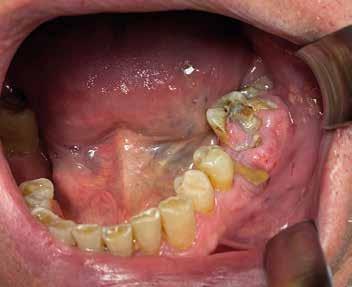

Deve prevedere sia l’osservazione sia la palpazione di tutte le mucose orali, partendo da labbra, lingua, guance, per arrivare alla valutazione del tessuto gengivale dei fornici, del palato e la gengiva aderente. Se ne devono valutare colore (fig. 11 ittero mucoso), fragilità, consistenza e presenza di ulcere o tumefazioni.

L’esame clinico rappresenta sicuramente la fase di analisi più complessa in quanto i parametri da valutare sono molti e possono interessare tutte le specialità odontoiatriche. Sono da valutare lo stato di salute della dentatura residua, la presenza o meno di manufatti protesici, il rapporto intermascellare,

lo stato di igiene orale, la condizione dei tessuti parodontali, le abrasioni dello smalto che ci indirizzino verso la diagnosi di parafunzioni come il bruxismo, la limitazione nell’apertura della bocca o la presenza di deviazioni per disordini temporo-mandibolari. (Figg. 16-21)

FIG. 17 FIG. 16 FIG. 19 FIG. 18 FIGG. 16-21: Valutazione FIG. 21 FIG. 20